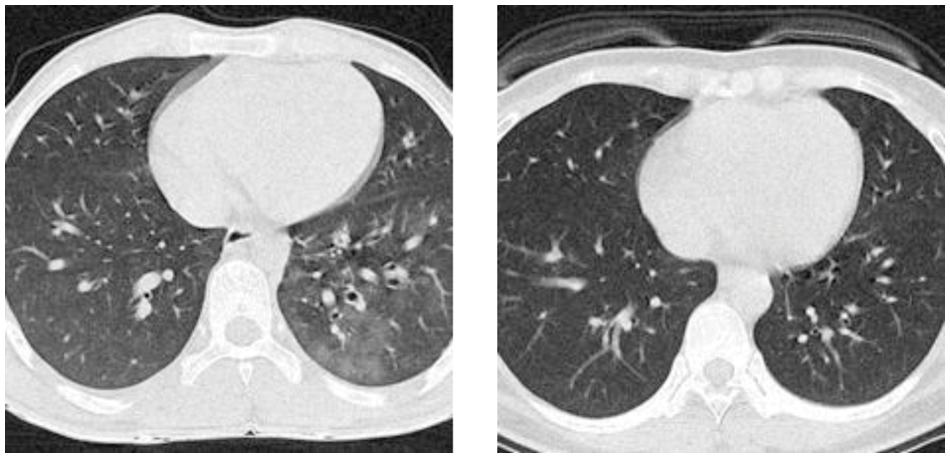

Figure 2: Examples of the preprocessed image set

The parameters of this study are listed in Tab. 3. The sizes of the original images are